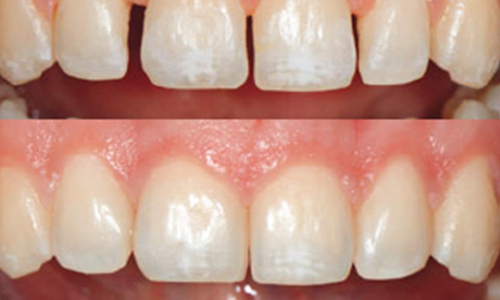

Early manifestation of decay is discolored surface of tooth. This is the demineralized portion of enamel (outer layer of tooth). This is mostly irreversible process requiring restorative treatment. If not treated at this stage, the decay may further involve dentin and pulp requiring more invasive procedure like root canal treatment.

Modern dentistry has introduced various tooth colored materials which are used for treatments like tooth decay, tooth fracture, diastema closure, smile designing.